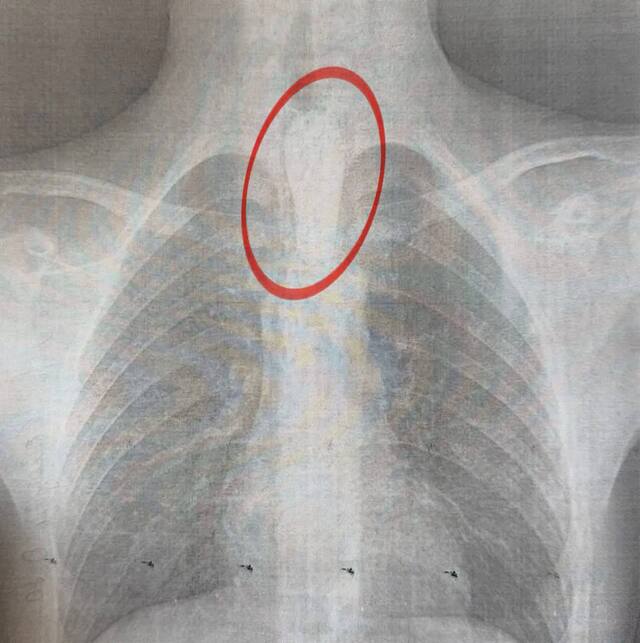

Хлопець ледь не задихнувся після того, як великий шматок м’яса застряг у його стравоході.

Він не міг ані ковтати, ані дихати, і почалась сильна слинотеча.

Операція, що тривала близько години, дозволила видалити шматок м’яса поетапно, аби не пошкодити стінки стравоходу.